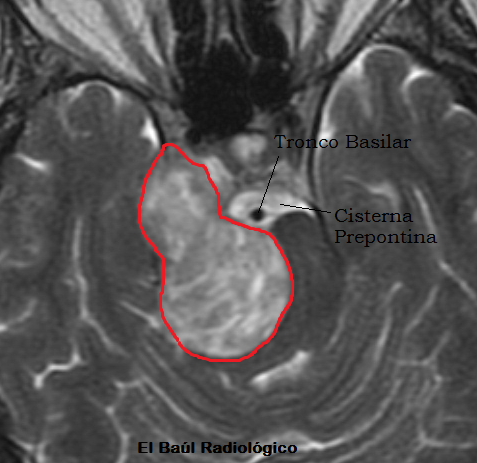

FIGURA 1) El pajaro estaba formado por dos partes. Una sólida delimitada por la línea roja y la cabeza por la cisterna prepontina.(The birdwas composed oftwo parts.A solid onebounded bythered line and thehead formed by theprepontinecistern).

De Doña María siempre habían dicho que tenía muchos pájaros en la cabeza, por eso no me extrañé al examinar las imágenes de la Tomografía por Resonancia Magnética craneoencefálica que le habían practicado. No es cierto que tuviera muchos pájaros, tan solo uno; acurrucado junto al tronco del encéfalo. El animal, miraba fijamente con su ojo negro y profundo, como si tuviera miedo y fuera a salir volando en cualquier momento. Por su aspecto, pico afilado, el pecho ahuecado y la cola desplegada me recordó al ave del paraíso.